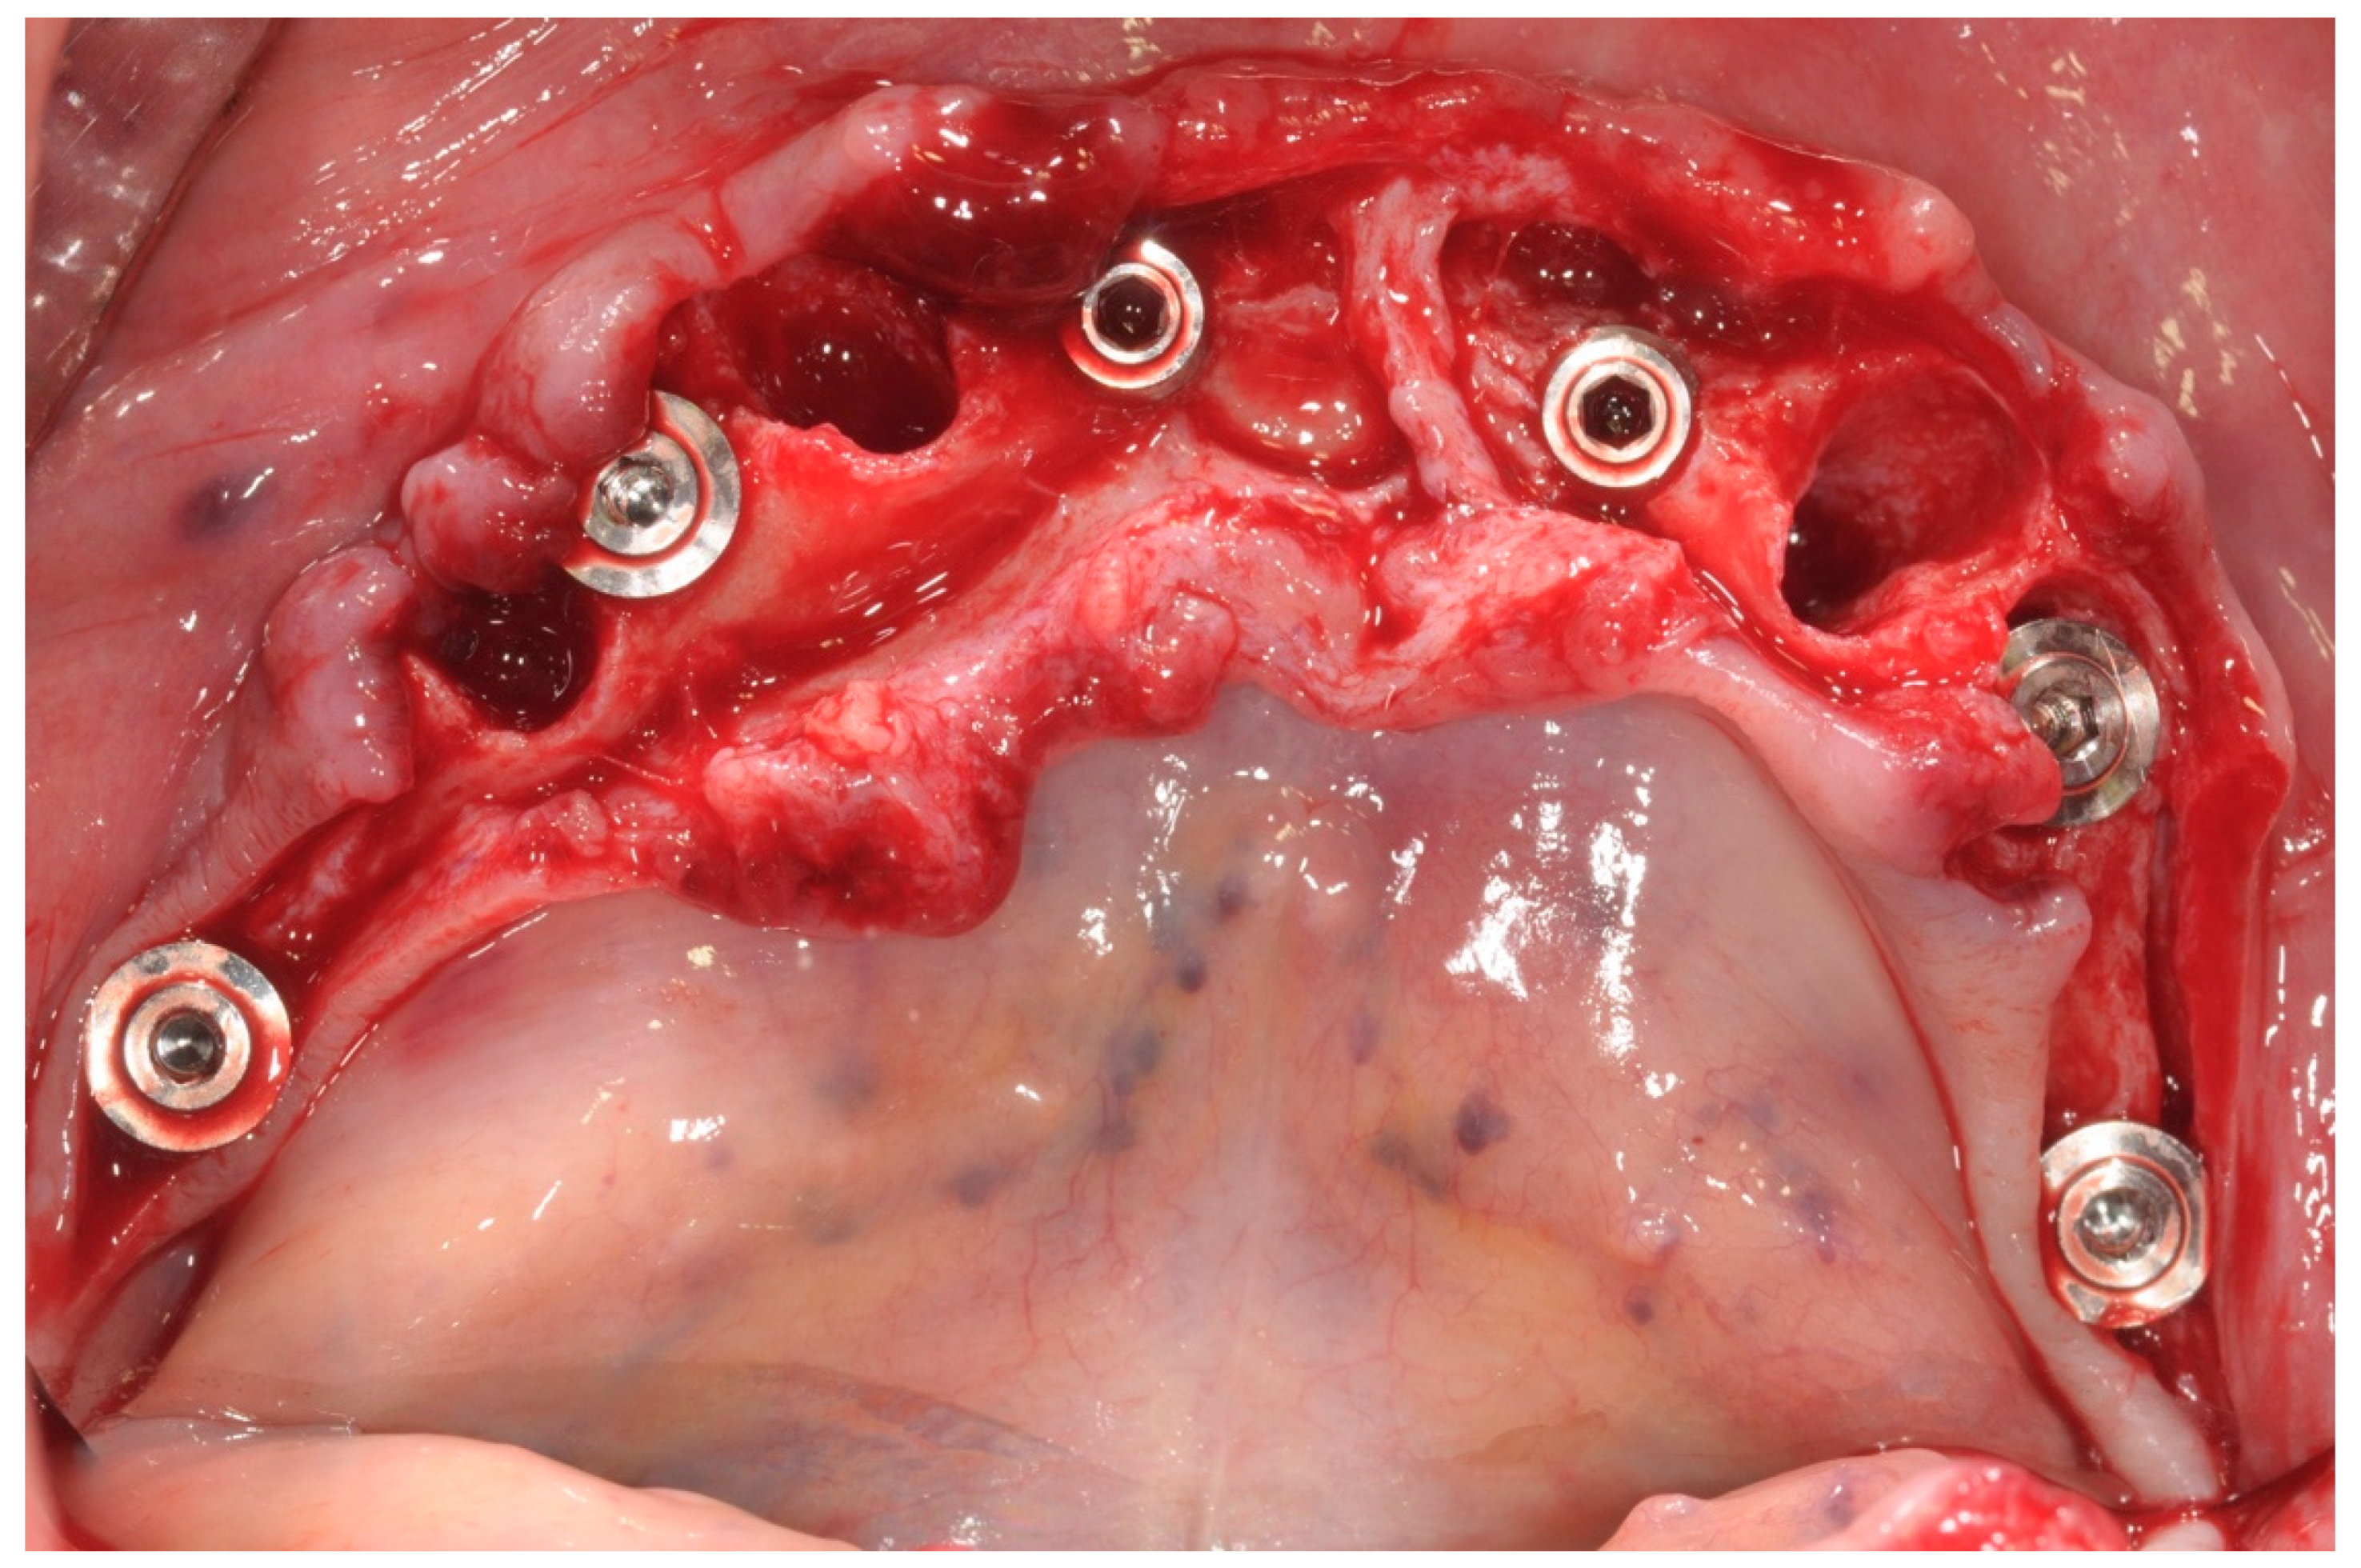

All patients enrolled in this study had panoramic radiographs and/or cone-beam computed tomography (CBCT) (Figure 1).

Figure 1. Preoperative panoramic X-ray.